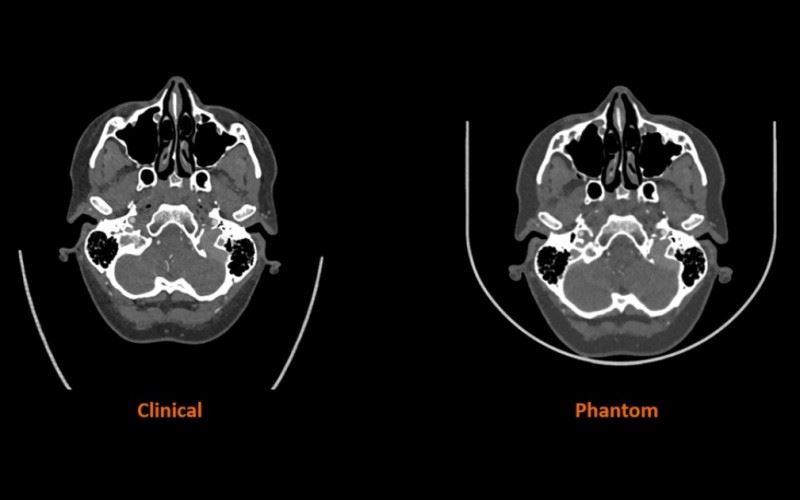

精準醫療3D時代,CT掃描新境界

3D列印機製造商Stratasys與西門子Healthineers合作研究,目標改進電腦斷層掃描(CT)掃描所使用的醫學成像模型,凸顯電腦斷層掃描(CT)成像在全球醫院中的重要性,那麼3D列印技術又是如何從中幫助?